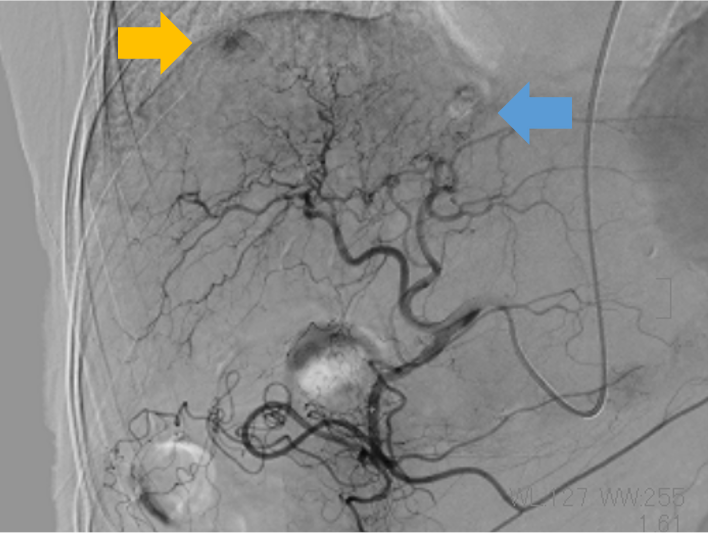

動脈塞栓術

腫瘍を栄養している動脈や出血している動脈を塞栓物質で詰めて治療することです。当院で行っている冠動脈化学塞栓療法(TACE)は、がん細胞(腫瘍)に酸素や栄養素を供給している動脈を抗がん剤と塞栓物質で塞栓します。主にX線CT装置と一体になった血管造影装置(IVR-CT装置)で検査・治療を行いっており、 X線CT装置を使用して腫瘍の栄養血管を同定し、3D画像を作成することで、血管の走行や目的血管を立体的に描出し、手術支援を行っています。その他に、骨盤骨折や喀血などで出血している血管をコイルなどで詰めて止血します。

| 肝動脈DSA画像 | X線CT-3D画像 |